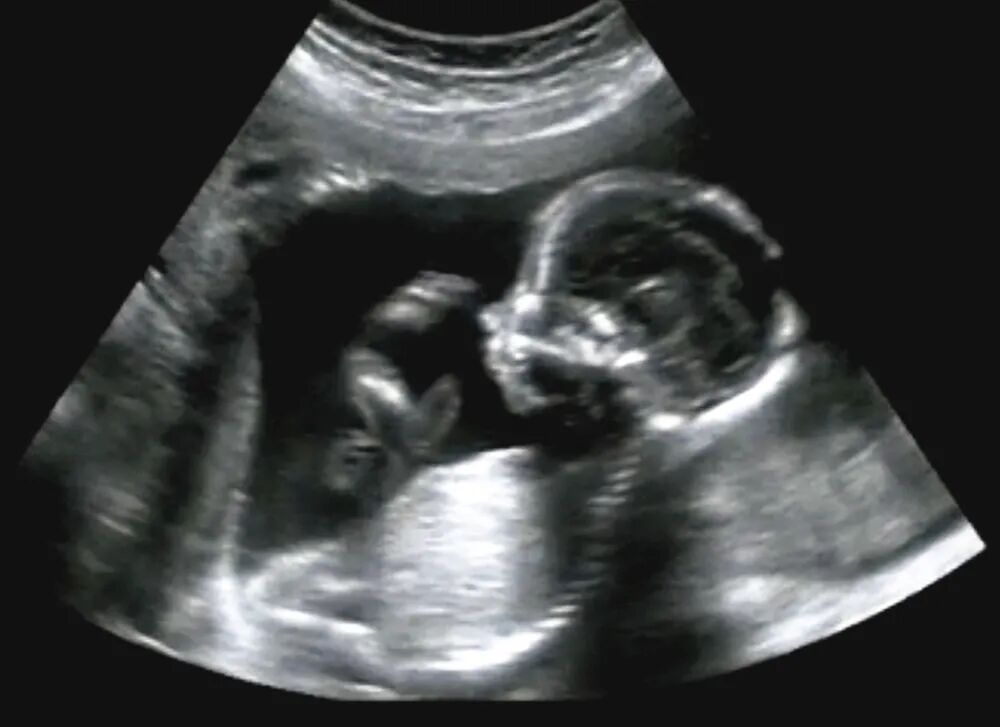

二维B超是最基本的B超成像技术。它通过探头发射超声波,接收回声,再将回声转换为二维平面的图像显示组织的结构和形态,有助于进行病变的检查和定位。

三维B超是指B超图像能够在第三个维度上显示。它能够通过探头在不断移动和旋转的过程中获取多个切片的二维图像,再将这些图像重建成立体的三维图像

相比于二维B超,它可以更直观地显示组织的立体形态,尤其对于复杂病变的诊断具有更强的优势。